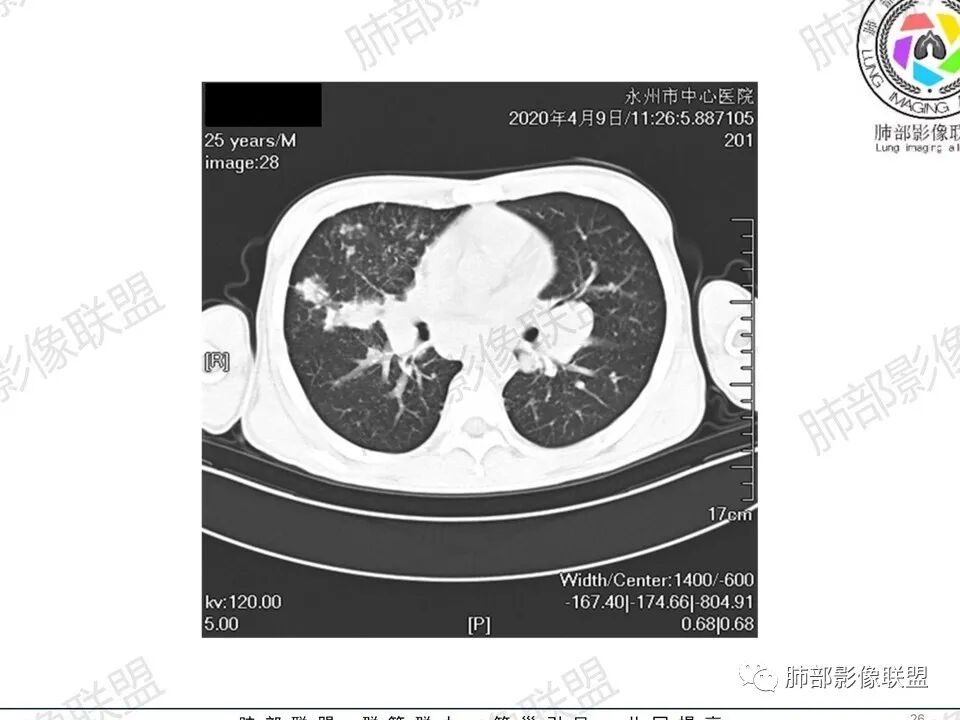

那个人:青年男性,慢性病程,咳嗽气促,伴盗汗胸痛。实验室,贫血,血沉快,C反应蛋白升高,低蛋白血症。影像,双肺散在斑片影,结节影,伴树芽,斑片影源支气管血管束分布,支气管走形自然,结节影有小空洞,有些周围有磨玻璃成分,小结节有些成串珠样改变,纵隔肺门淋巴结肿大,心腔低密度。考虑淋巴增值类疾病,结核?淋巴瘤?结节病?鉴别血管炎,实验室,影像不太支持

穿越七海的风:双肺多发结节斑片影,支气管通畅,间质浸润,纵隔肺门肿大淋巴结,考虑淋巴瘤?白血病浸润?结节病?

薏米:青年男性,慢性咳嗽,咳痰,气短,贫血,淋巴细胞低,尿隐血阴性,双肺散在多发结节,斑片,树芽影,支气管充气,肺门,纵隔淋巴结肿大,融合趋势,考虑淋巴瘤,鉴别结核

甄德强:年轻男性,慢性起病,双肺多发斑片影,结节影及粟粒点状影,纵隔及双肺门淋巴结肿大,似乎密度不均,结核中度症状,血沉快,一元论考虑结核,鉴别诊断结节病。

一切∮随缘:双肺多发大小不等结节,结节密度高,边缘清楚,部分结节内可见血管穿行,另右肺长条状实变影,内部可见支气管充气征,局部支气管壁增厚,双肺多发小树丫,双肺门及纵隔淋巴结肿大,部分融合,无增强,对淋巴结坏死无法判断,临床:年轻男性慢性病史急性加重,血象、CRP、ESR高,考虑一元论:结核(年龄加影像都符合),二元论:结节病或淋巴瘤+结核(建议CT增强及淋巴结穿刺),无原发肿瘤病史,癌性淋巴管炎代排。

刘L:纵隔多发淋巴结肿大,自肺门向上呈对称性分布,部分融合,内密度均匀;双肺散在分布大小不等结节,边界清晰,右肺中叶部分伴有实变,首先考虑结节病,建议增强扫描排除肺结核。

男性,25岁,咳嗽咳痰1年,气促两月,加重一天,伴盗汗胸痛。CT示双肺散在斑片影,结节影,树芽征,部分周围伴磨玻璃影,以右肺上叶明显,纵隔及双肺门可见多发淋巴结肿大,部分融合,青年人,病史较长,首先考虑结核,不排除结核合并结节病可能。

3、影像表现:双肺散在斑片影及结节影,部分结节内可见血管穿行,斑片影沿支气管血管束分布,近胸膜侧病变收缩不明显。部分中央淋巴间质增厚,小叶间隔增厚。病灶内支气管穿行,部分支气管略扩张。局部小结节呈串珠样改变。纵隔、肺门区、锁骨上及腋窝淋淋巴结肿大,部分有融合。心腔低密度。脾大。

2.双肺多发片影及结节影,边界可分辨,右肺中上叶较为密集,没有胸膜下分布优势。病灶实性密度为主,未见钙化及液化。

3.右肺较多微小结节,密度较为浅淡,部分沿血管束分布,未见沿小叶间隔及叶间裂分布结节影,未见典型的终末气道树芽。

4.病灶区域穿行支气管显示良好,未见壁增厚及管腔狭窄。

5.双肺门及纵隔淋巴结显著增大,这改变相当显眼。这里强调“双肺门”及“多发”!